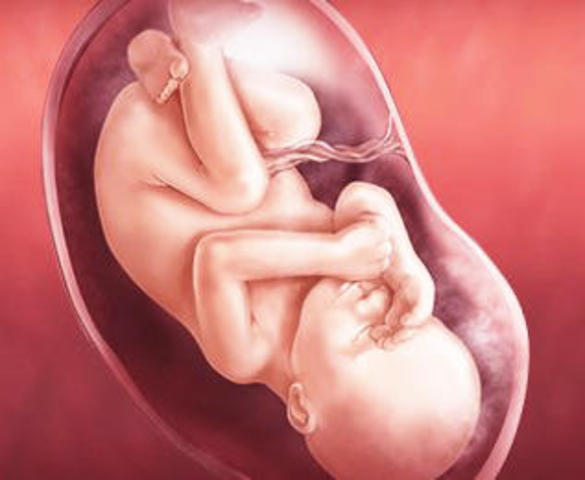

El feto a estas semanas empieza a ubicarse en la posición definitiva que tendrá al nacer, que en la mayoría de los casos es con la cabeza hacia abajo a pesar de que puede cambiarla hasta el momento del parto. En algunos caso los fetos se posicionan de nalgas o situación transversa debido a una falta de movilidad por un cordón umbilical corto o enredado en el feto, por la forma del útero materno o simplemente porque se siento mucho mejor en esa posición.

Ahora el bebé engorda a razón de 200 a 300 gramos a la semana, por lo que su aspecto exterior cambia considerablemente: cada vez es está más rellenito.

Su cabeza está proporcionada con respecto al resto del cuerpo, aunque hay que tener en cuenta que los niños tienen la cabeza más voluminosa que los adultos.

Las uñas han completado su desarrollo y si es un chico sus testículos ya se encuentran dentro de la bolsa escrotal.